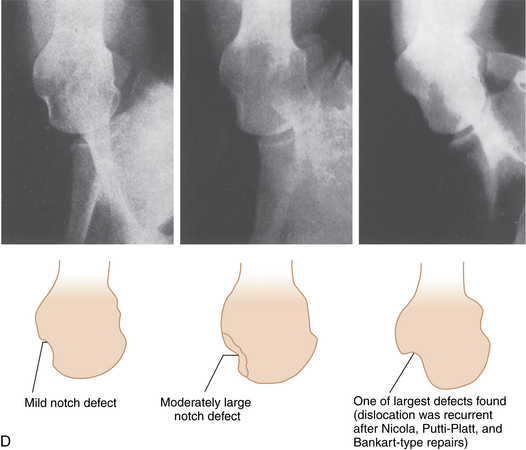

Shoulder (Stryker notch view) | Radiology Reference Article | Radiopaedia.org West point and Stryker notch views for anterior shoulder dislocations (animated) - YouTube G. Stryker notch view. | Download Scientific Diagram a Patient position for the Stryker notch view. b Radiograph of Stryker... | Download Scientific Diagram | Stryker View Shoulder

![Stryker View Shoulder 722, 392 PDF] Audit on radiographs in anterior shoulder dislocations. | Semantic Scholar](https://d3i71xaburhd42.cloudfront.net/357130d49c10422673c4c8802b32417def7deb06/3-Figure2-1.png)